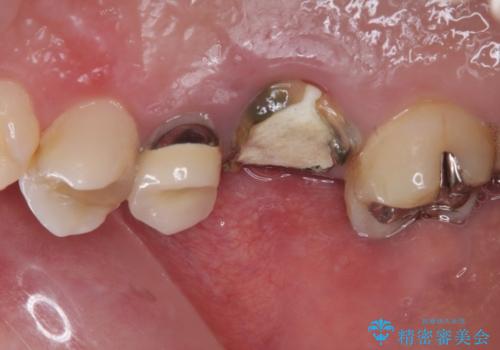

- 近医にて治療がなかなか進まないとのことで来院された患者様です。

詰めている材料を外したところ、目視で確認できるほど割れており、要抜歯との説明をし、インプラント治療を行うこととしました。

骨量が十分にあることが3次元CTより確認されたため、事前に仮歯を用意した上で、抜歯即時埋入インプラントによる補綴治療を行うこととしました。